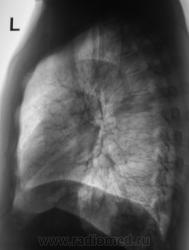

При расшифровке флюорограмм пациент "взят на контроль". Жалоб пациент не предъявляет. Подняли "архив", флюорограмма за 2009 г. - "норма".

Произвели стандартное дообследование.

Томограммы.